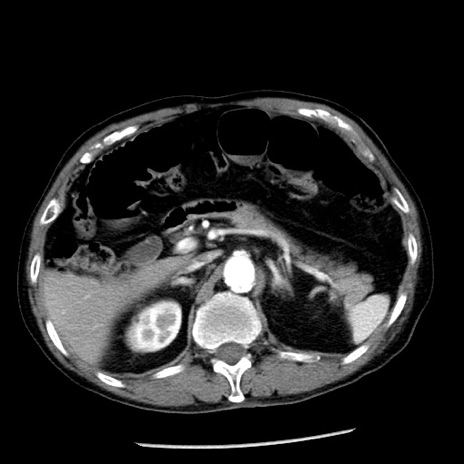

症例26(横断像)

【症例】80歳代男性

【主訴】嘔吐

【現病歴】昨晩2回嘔吐あり、今朝になっても嘔吐あり。来院。

【既往歴】胃潰瘍

【身体所見】意識清明、BT 37.6℃、BP 166/95mmHg、HR 100bpm、SpO2 97%、腹部:平坦・軟、腸蠕動音聴取良好、圧痛なし。

【データ】WBC 21900、CRP 1.46